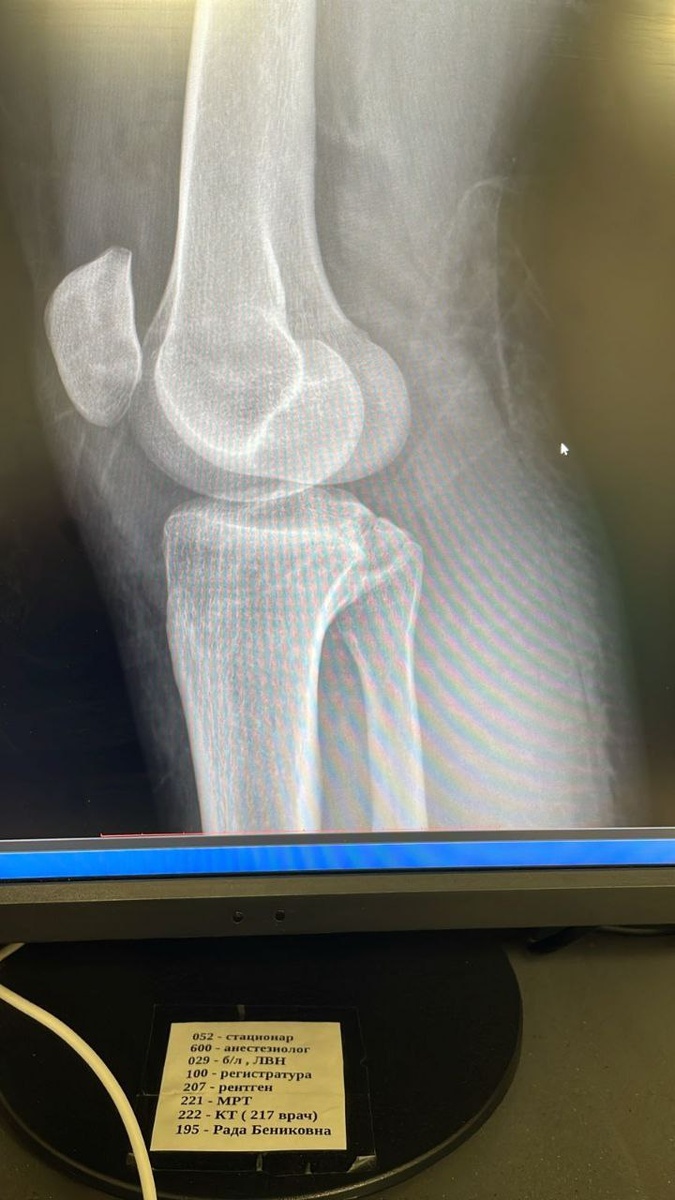

Пациентка подвернула ногу. Обратилась по месту жительства в травмпункт в области. Ее осмотрели, сказали, что перелома не видят, но, спасибо травматологам, заподозрив разрыв связок, на всякий случай, наложили гипсовую лонгету, и отпустили домой. Пациентка обратилась к нам самостоятельно. При обследовании был выявлен оскольчатый внутрисуставной импрессионный перелом наружного мыщелка большерцовой кости со смещением отломков. Суставная поверхность, если заметите на снимках, разлетелась как стекло, на мелкие кусочки. Пациентку быстро обследовали и подготовили к оперирации. Была проведена артроскопия коленного сустава, и остеосинтез пластиной по контролем артроскопии. Пациентке повезло! К счастью, она вовремя обратилась. Чем позже в таких случаях, тем сложнее исправить ошибки. А при первичных снимках возможно не увидеть перелома, так как все еще свежее, и линия перелома может не проявиться, если нет смещения.